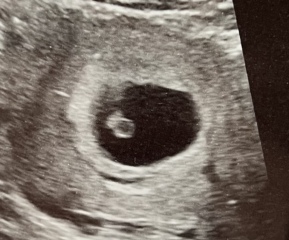

Jewellerycookiesandcream · 27/06/2024 20:20

I’m current pregnant with mono di twins (identical) and had an early scan at 7 weeks ( attached). In my case the sonographer could tell straight away they were twins and also that they were sharing a placenta so were mono di. Xx